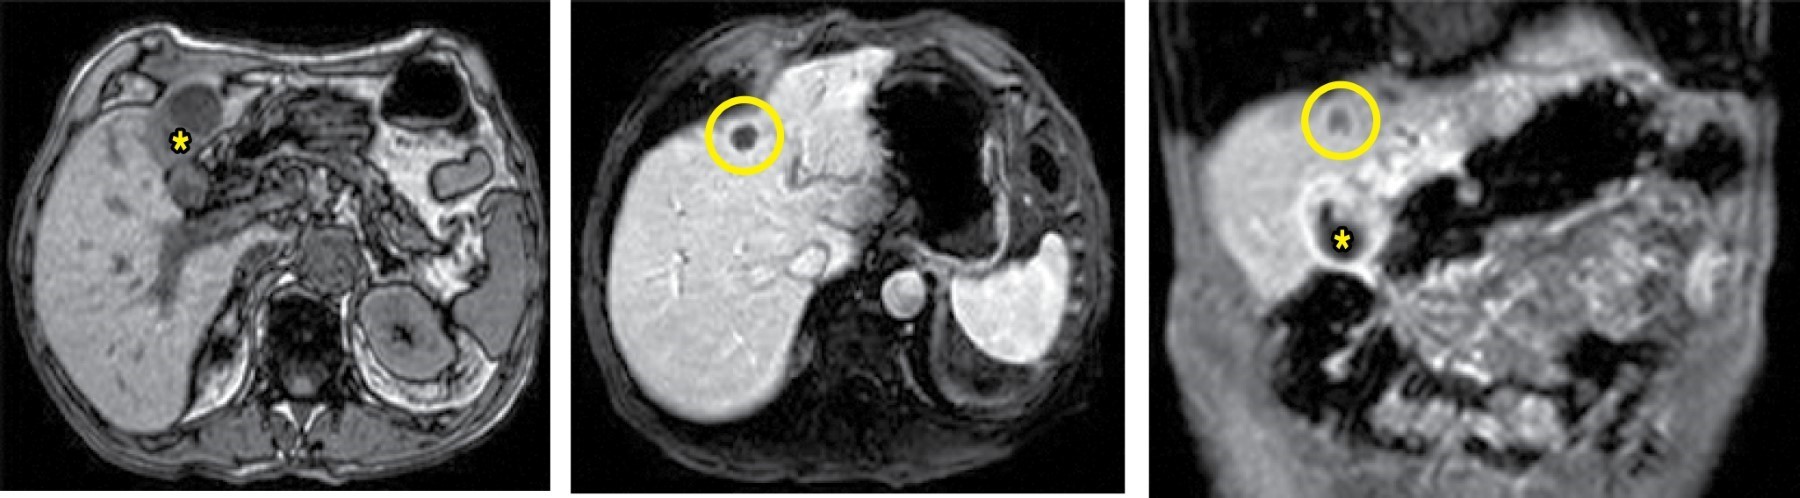

Case 2. An 87-year-old man is dependent for basic activities of daily living (BADL). He had a history of myasthenia gravis, hypothyroidism, vasculopathy with chronic ischemia of the lower extremities, and a myocardial infarction, as well as an episode of acute cholecystitis treated conservatively five years earlier. He consulted for a painless mass in the RHC of a year and a half of evolution, with spontaneous suppuration during the last week. On examination, the mass had a diameter of 20 cm and a small solution of continuity. An abdominal CT scan showed chronic calculous cholecystitis complicated by an abscess in the abdominal wall fistulizing to the skin surface (Figure 2).

A percutaneous drainage of the abscess was performed, and AB treatment was given. A subsequent magnetic resonance (MRI) cholangiography reported a small liquid collection of 4 × 1 cm in the right anterosuperior abdominal wall with small gallstones inside, a collapsed gallbladder with cholelithiasis, and no clear evidence of a fistula, in addition to the absence of alterations in the intrahepatic and extrahepatic biliary tract. The scarce secretion, but maintained through the drainage, motivated the maintenance of this drainage, until after four weeks it presented an accidental exit, so it was decided not to reposition the liquid lost. Subsequent evolution was favorable. Definitive treatment was discarded due to the high anesthetic risk.

Figure 2